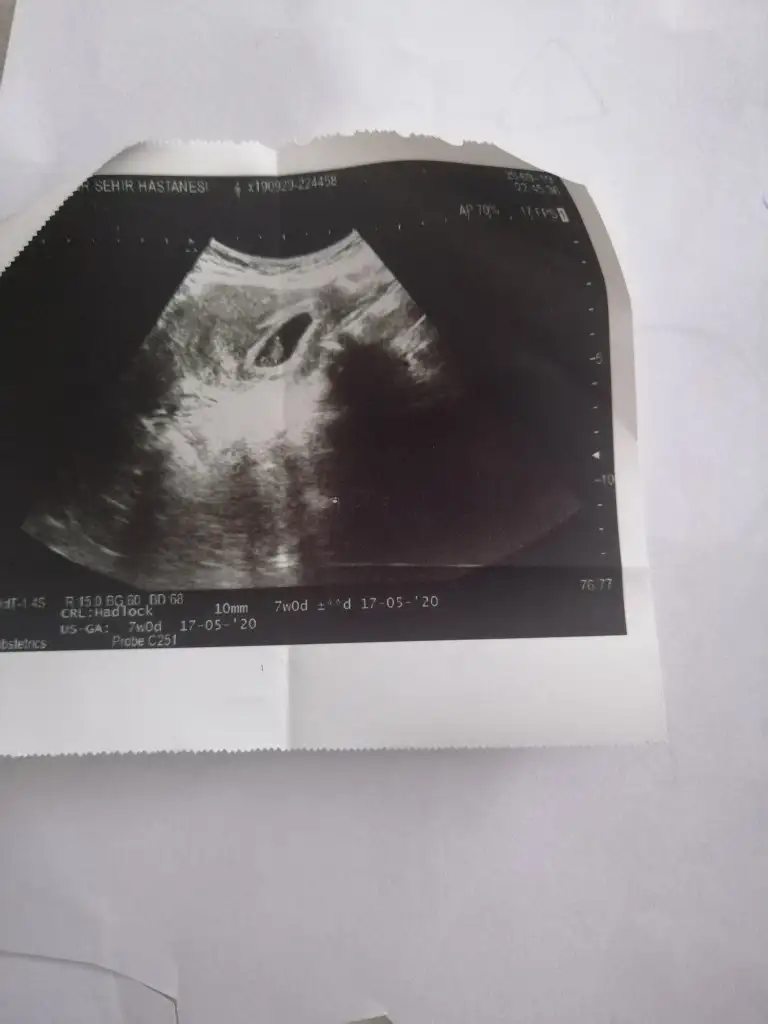

Banada erkek demiştiniz hatta baya net erkek demiştiniz kız diyince doktor şaşırmıştınız bnde çok şaşırmıştım tabi çünkü baya umutlanmıştım 2 kızım var doğal olarak değişik olsun istemiştim tabiki Rabbim in dediği olur ama hala erkek hissediyorum ayrıntılıda pozisyonu tersti cinsiyeti gözükmüyor demişti perinatolog ama 2 doktor kız gibi biride düşük kalitede bir cihazda kız demişti sonra rüyamda bebeğimin isminin koyulduğunu gördüm mavi nüfus kağıdında Ali arif yazıyordu bilemiyorum hala erkek hissediyorum pembe kıyafetleri almama rağmen

az kaldı sonucu görmeye herşey den önce Rabbim sağlıklı ve hayırlı evlatlar nasip etsin bizlere